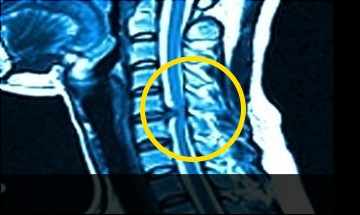

Виды и стадии межпозвоночных грыж в шее

Симптомы и лечение грыжи шейного отдела позвоночника . Что такое грыжа шейного отдела позвоночника . Виды и стадии межпозвоночных грыж в шее .

Что такое межпозвоночная грыжа шейного отдела . Причины развития, симптомы, виды и диагностика . Удаление и лечение грыжи без операции .

Грыжа диска может стать причиной компрессии нервного корешка с развитием радикулопатии только у 2-5% пациентов . Грыжа шейного отдела позвоночника: симптомы Острый период . . .

Как образуется грыжа? Грыжа шейного отдела может развиваться в течение долгого времени или образоваться внезапно . Врачи называют несколько причин возникновения данной проблемы